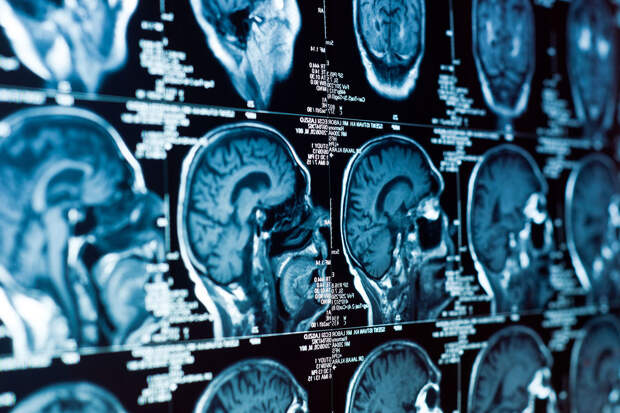

Ученые из Университета Тасмании установили, что люди с низким социально-экономическим статусом на 33% чаще переносят инсульт по сравнению с более обеспеченными слоями населения. Результаты исследования опубликованы в Journal of Stroke and Cerebrovascular Diseases.

Анализ показал, что социальное положение напрямую связано с риском развития заболеваний сосудов. В частности, выяснилось, что люди с низким социально-экономическим статусом на 33% чаще страдают от инсультов.По словам исследователей, у людей с низким уровнем дохода чаще встречаются гипертония, сердечные патологии, диабет и нарушения обмена веществ. В таких группах населения также чаще диагностируются болезни пищеварительной и иммунной систем, а иногда и онкологические заболевания — даже в молодом возрасте.